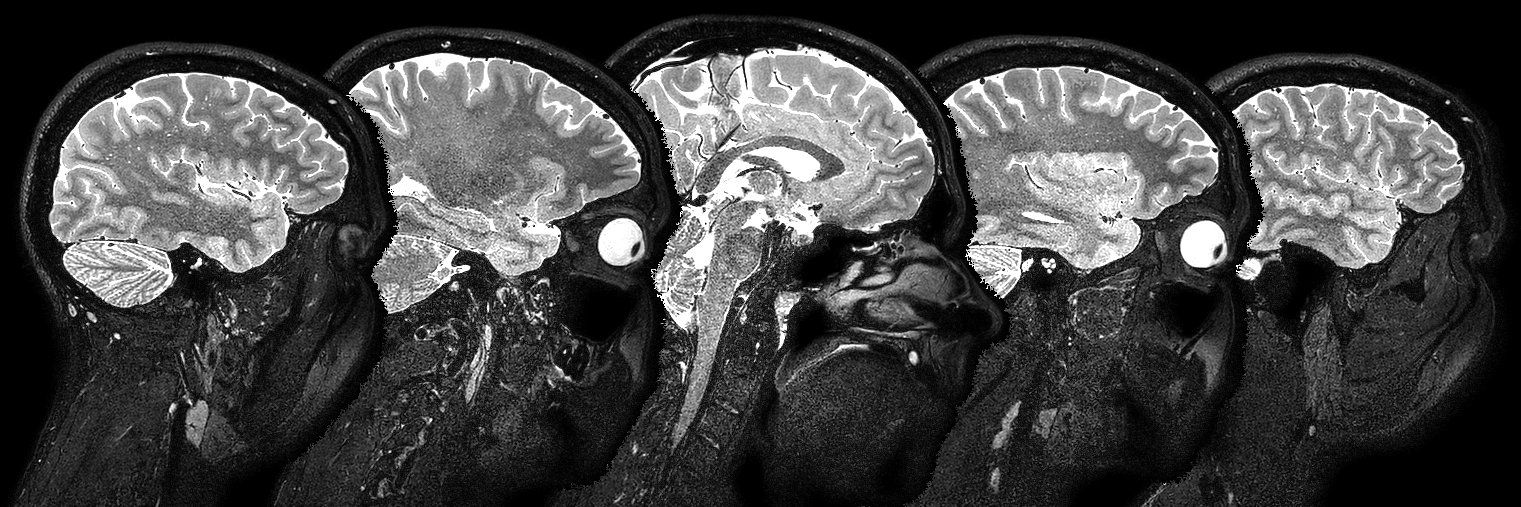

Renal MRI Physicist @SPMIC_UoN, climber, musician, and live sound engineer. Basically I enjoy magnets, rocks and loud noises.